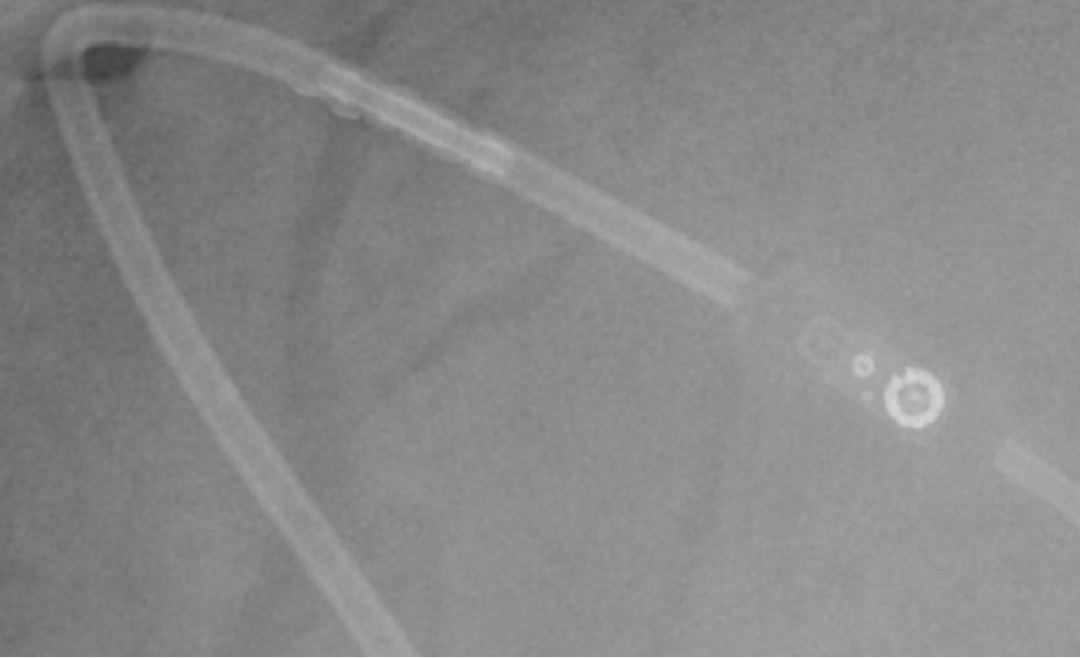

2015-2-10 X线